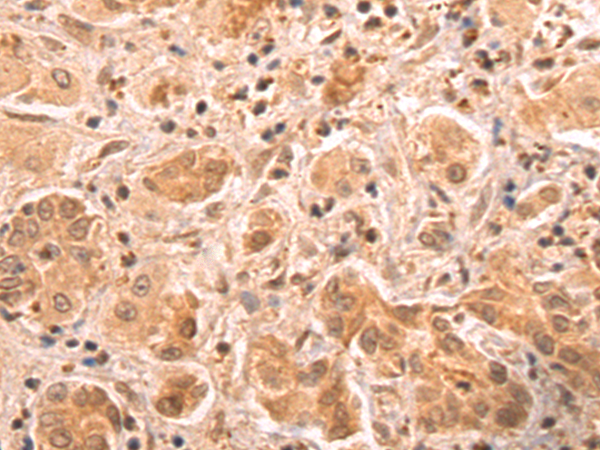

分类: 科研抗体货号: P11197别名: ARC34; PRO2446; p34-Arc; PNAS-139应用: WB,IHC反应种属: Human, Mouse, Rat